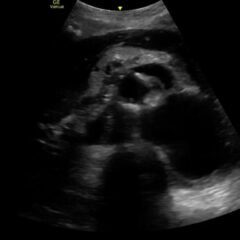

Small bowel diverticulitis is an uncommon subset of acute diverticulitis and can mimic many other intra-abdominal processes. As a result, imaging modalities such as ultrasound and computed tomography (CT) scan are especially important for timely recognition of diverticulitis and can expedite diagnosis and treatment and reduce complications. In the case described in this report, an 81-year-old male with history of esophageal cancer and recurrent diverticulitis with history of multiple bowel resections presented to the emergency department (ED) with right lower quadrant abdominal pain and constipation. Findings on ultrasound were suggestive of diverticulitis, and findings on CT of the abdomen and pelvis showed ileitis with phlegmon and micro-abscess suspicious for small bowel diverticulitis. ED providers should familiarize themselves with ultrasound findings of diverticulitis and be aware that diverticulitis can also present in the small bowel. Treatment of small bowel diverticulitis is similar to colonic diverticulitis.